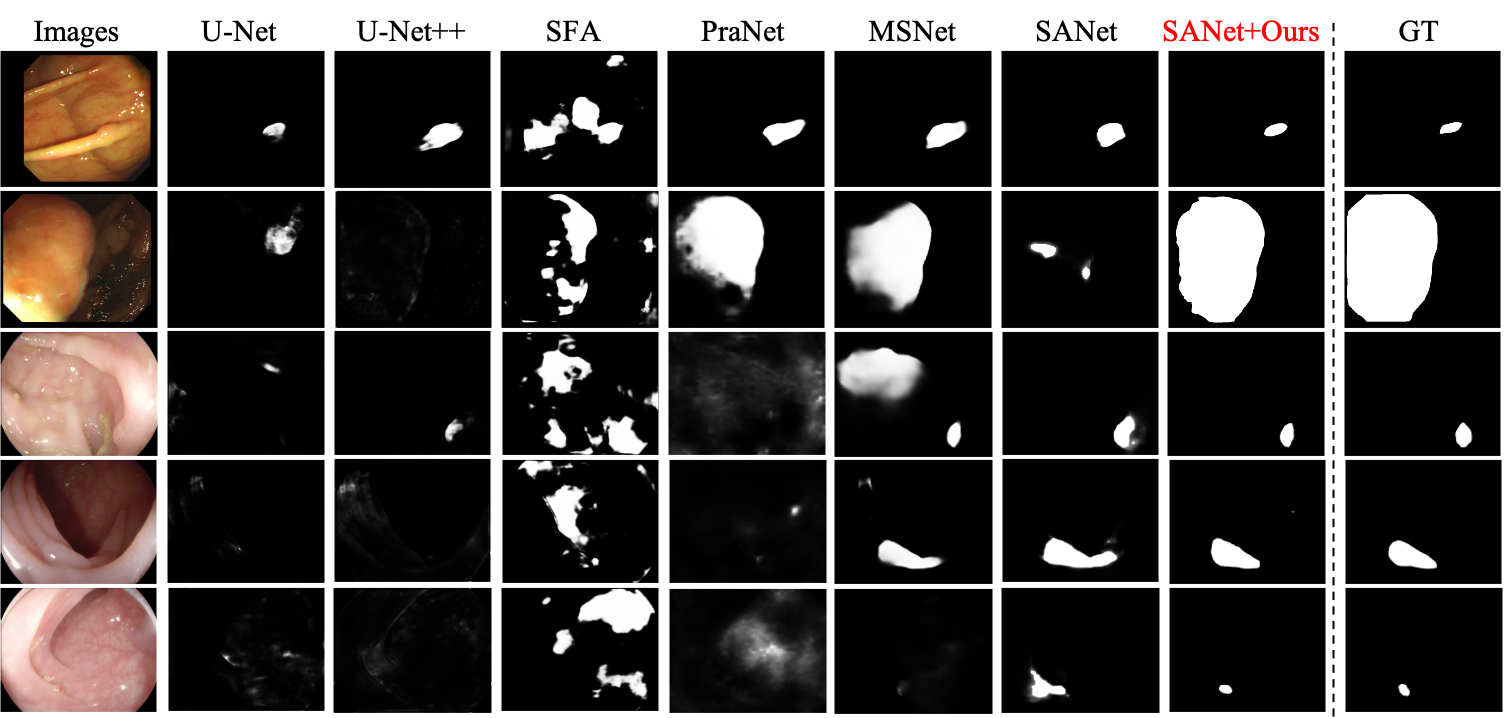

4.3 Visual Comparison

Fig. 5 visualizes some predictions of different models. Compared with other counterparts, our method not only clearly highlights the polyp regions but also suppresses the background noise. Even for challenging scenarios, our model still handles well and generates accurate segmentation mask.